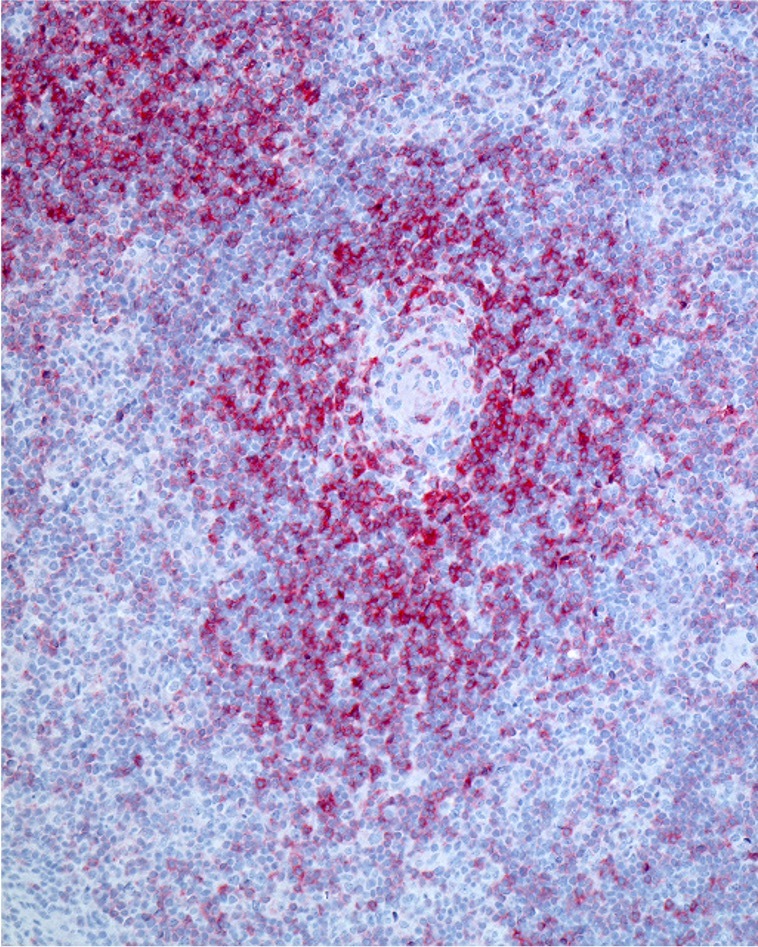

Ziel des Projekts ist, die Heilungschancen von Betroffenen deutlich zu erhöhen. Die Beteiligen möchten durch den smarteren und zielgenaueren Einsatz bekannter Therapien die Behandlung von T-Zell-Non-Hodgkin-Lymphomen verbessern, einer oft aggressiven Form von Lymphdrüsenkrebs. Solche T-Zell-Lymphome entstehen aus fehlgesteuerten Abwehrzellen des Immunsystems.